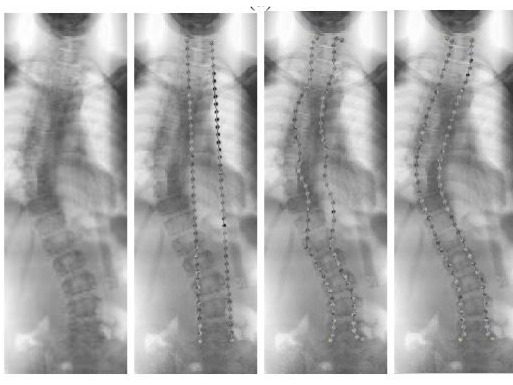

SCPM pada penentuan tulang belakang penderita skoliosis dari awal (kiri) hingga partikel sempurna mengikuti tulang belakan (kanan)

Dengan kesempurnaan uji cobanya, pria kelahiran Surabaya ini menerangkan metode ini telah diterapkan pada bidang kedokteran, yaitu mendeteksi kelengkungan tulang belakang. Pada pengujian tersebut tampak partikel bermuatan positif bergerak mengikuti bentuk citra tulang belakang penderita skoliosis yang digunakan. Partikel-partikel membuat segmentasi pada citra tulang belakang dan memudahkan tenaga medis dalam melakukan diagnosisnya.